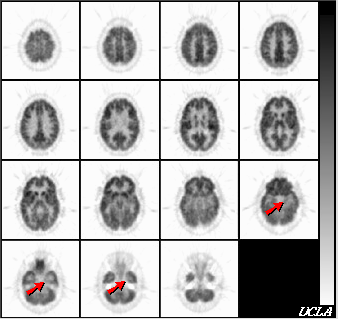

The hypometabolism in the left mesial temporal region (arrows) is consistent with a seizure focus. No other foci are seen.